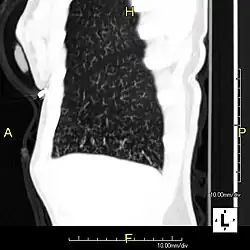

Sagittal reformatted CT image showing "tree in bud" appearance of impacted distal small airways in primary ciliary dyskinesia | |

In radiology, the tree-in-bud sign is a finding on a CT scan that indicates some degree of airway obstruction.[1] The tree-in-bud sign is a nonspecific imaging finding that implies impaction within bronchioles, the smallest airway passages in the lung. The differential for this finding includes malignant and inflammatory etiologies, either infectious or sterile. This includes fungal infections, mycobacterial infections such as tuberculosis or mycobacterium avium intracellulare, bronchopneumonia, chronic aspiration pneumonia, cystic fibrosis or cellular impaction from bronchovascular spread of malignancy, as can occur with breast cancer, leukemia or lymphoma.[2] It also includes lung manifestations of autoimmune diseases such as Sjögren syndrome or rheumatoid arthritis.[3][4]

Histopathologic studies have shown that the tree-in-bud pattern is caused by demarcation of the normally invisible branching course of the peripheral airways, which usually results from bronchioles being plugged or blocked with mucus, pus or fluid. In addition, dilated and thickened walls of the peripheral airways and peribronchitis can make the affected bronchioles more easily visible, as is seen in patients with cystic fibrosis.